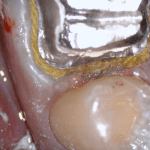

An old PFM crown warranted replacement due to open margins and recurrent decay. After the crown was removed, the margins were refined and the tissue was displaced with expasyl and retraction cord.